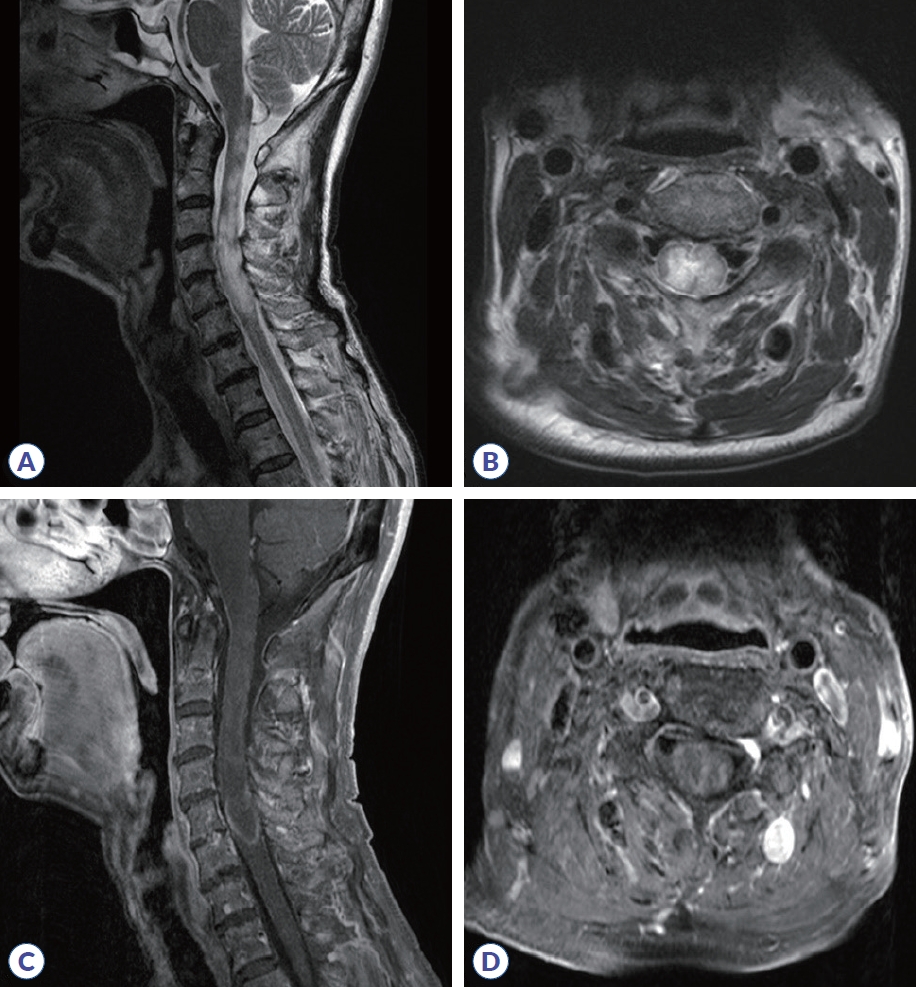

On admission, neurological examination showed normal alertness, language, and cranial nerve function. Sensory testing revealed hypesthesia involving all modalities below the C4 level, accompanied by right arm weakness (medical research council scale [MRC] 4/5-), and bilateral leg weakness (MRC 3/3), resulting in an expanded disability status scale (EDSS) score of 7.0. Deep tendon reflexes were brisk (+++) in the legs, with negative Babinski sign. Positive Lhermitte’s sign and truncal ataxia were present. While motor evoked potentials were normal, abnormal somatosensory evoked potentials in all limbs indicated a central sensory pathway deficit and electromyography suggested concurrent right brachial plexopathy. This suggests that sensory ataxia caused balance impairment and confounded clinical assessment of weakness. Cerebrospinal fluid (CSF) analysis showed 7 white blood cell count/μL (88% lymphocytes), protein 51 mg/dL (normal 8-43), and glucose 56.7 mg/dL (CSF/serum ratio 0.36). CSF VZV polymerase chain reaction (PCR) was negative, and the CSF FilmArray meningitis/encephalitis panel (Bio-Fire Diagnostics, Salt Lake City, UT, USA) meningitis/encephalitis panel was also negative. Following the prior clinical HZ diagnosis, CSF VZV IgG/immunoglobulin M (IgM) antibody titers were not obtained. Spinal magnetic resonance imaging (MRI) revealed cord swelling and T2 high-signal intensity from the C1-C6 level with inhomogeneous enhancement, consistent with longitudinally extensive transverse myelitis (LETM) (Fig. 1). Brain MRI was unremarkable aside from the known meningioma. Serologic testing revealed antinuclear antibody with a mitochondrial pattern at a titer of 1:160. All other tests were negative, including rheumatoid factor, anti-double-stranded DNA, antiphospholipid antibodies (including anticardiolipin IgG/IgM), antineutrophil cytoplasmic antibody, myelin oligodendrocyte glycoprotein antibody, and the paraneoplastic antibody panel. Anti-SS-A was borderline and anti-SS-B was negative. Cell-based assay (CBA) revealed a positive anti-AQP4 antibody (4+). Based on these findings, the patient was diagnosed with AQP4-positive NMOSD.

Figure 1.

Cervical spinal MRI. (A) Sagittal T2-weighted imaging shows diffuse cord swelling and hyperintensity extending from the cervicomedullary junction to the C6 level. (B) Axial T2-weighted imaging of the upper cervical level shows bilateral hyperintensity, more pronounced on the right. (C) Sagittal post-contrast T1-weighted imaging reveals patchy intramedullary enhancement in the cervical cord. (D) Axial post-contrast T1-weighted imaging shows inhomogeneous enhancement at the mid-cervical level. MRI, magnetic resonance imaging.